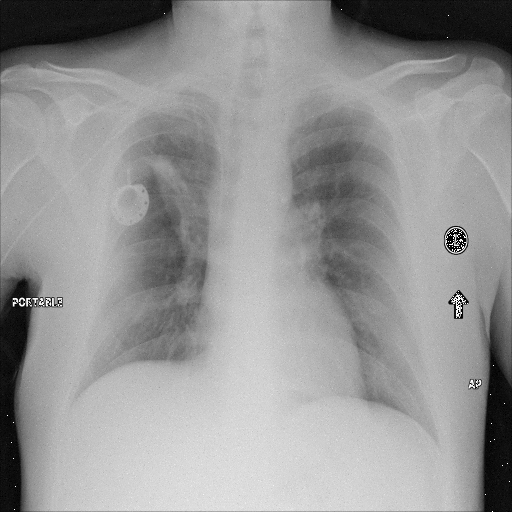

Refer to caption

(a) Original,

case 1 with a block.

(b) ϵ=102HWitalic-ϵsuperscript102𝐻𝑊\epsilon=10^{2}\cdot H\cdot W,

case 1.

(c) Original,

case 2 with a block.

(d) ϵ=102HWitalic-ϵsuperscript102𝐻𝑊\epsilon=10^{2}\cdot H\cdot W,

case 2.

Figure 4: Block obfuscation with DP-GLOW.

Here, we assume two possible privacy leakage scenarios. To CXR images, we intentionally add features that can lead to the re-identification of the subject appearing in a CXR image. The first feature is an artificial block marker. The second feature is a rare anatomical abnormality known as situs inversus simulated by flipping a CXR image along the vertical axis. Figs. 3(a) and 3(c) show CXR images with the artificial block marker. Fig. 5(a) shows a flipped CXR image to represent a case of situs inversus. We applied DP-GLOW to these CXR images. In Figs. 3(b) and 3(d), the image domain LDP fails to obfuscate the artificial block marker with a moderate privacy budget. In contrast, in Figs. 4(b) and 4(d), DP-GLOW successfully obfuscated the artificial block marker with the moderate privacy budget. On the other hand, the anatomical shape of the chest and the abnormal opacity (hilar regions in the case 1) are preserved. In Fig. 5(b), we observed that the right edge of the heart does not become obfuscated with the image domain LDP. In contrast, in Fig. 6(b), we observed that the right edge of the heart becomes obfuscated and the heart appears at the center of the thoracic cage with DP-GLOW. However, DP-GLOW with this privacy budget is insufficient to almost completely erase the feature of situs inversus.